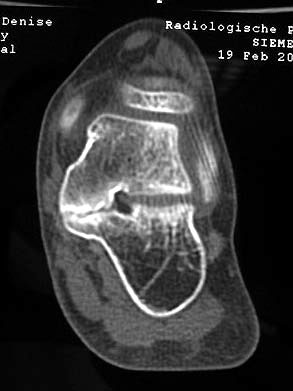

MRT und CT konkurrieren in der Fein-Darstellung der Knochenbrücke, der Beurteilung der nichtbetroffenen Anteile des Subtalargelenkes und der Sekundärveränderungen. Das MRT bietet den Vorzug, bindegewebige und knorpelige Strukturen (Abb. 2) und bei Einsatz von Kontrastmittel auch knöcherne Aktivierungsphänomene genau abzubilden; die knöcherne Feinstruktur und genaue Ausdehnung dagegen ist mit dem Dünnschicht-CT wesentlich exakter darstellbar (Abb.3). In manchen Fällen ist eine 3-D-Rekonstruktion des CT hilfreich. Besonders wichtig ist eine geeignete Schichtebenen-Wahl:

• Frontalschnitte etwa im rechten Winkel zur Auftrittsfläche und im Bereich des Subtalargelenkes bis weit nach dorsal geführt

• Transversalschnitte besonders für das Talonaviculargelenk

Diagnostisch sollte neben Röntgenübersichtsaufnahmen (indirekte radiologische Zeichen: Dorsaler Traktions-Osteophyt am Taluskopf, „talar beaking“; kontinuierliche Linie der Trochlea-tali-Kontur übergehend in die Sustentaculum-tali-Kontur, „C-Zeichen“ (Abb. 11) 10) immer die dreidimensionale Bildgebung eingesetzt werden. Das MRT (mit Kontrastmittel) kann die Struktur der Brückenbildung und z.B. die Qualität des Restgelenkes (Knorpel-Dicke) besonders gut abbilden; das Dünnschicht-CT zeigt die knöcherne Feinstruktur im Bereich der Coalitio und den oft sehr schrägen Spalt-Verlauf im Frontalschnitt dagegen häufig genauer. Meist findet sich die Überbrückung im Bereich der medialen Facette; die Schichten sollten jedoch bis weit nach dorsal beurteilt werden, da ansonsten dorsomediale Formen übersehen werden können. Rozansky et al 7 unterschieden fünf morphologische Typen auf der Basis von 3-D-CT-Rekonstruktionen. Allerdings ist eine prognostische Zuordnung bisher nicht möglich.